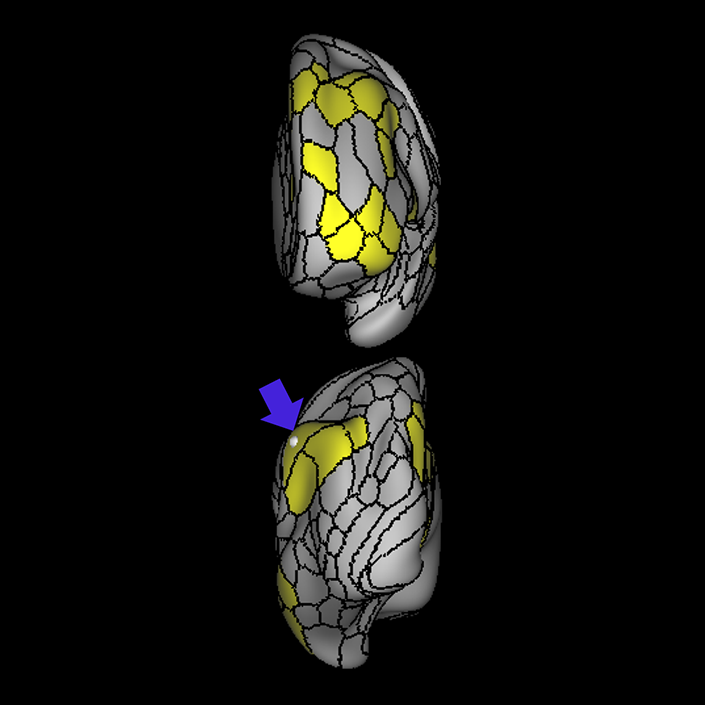

ᐅ SummaryArea 44: part of the inferior frontal gyrus of the lateral frontal lobe. Translates abstract and intentional information in the prefrontal cortex to more detailed representations to help guide the production of verbal and manual actions. In addition to its known association with Broca's area, is sometimes represented as part of Broca's complex ᐅ Where is it?Area 44 is at the posterior most part of the inferior frontal gyrus. It is the anterior bank of pars opercularis of the IFG. ᐅ What are its borders?Area 44 borders area 45 anteriorly and area 6r posteriorly. Area 8C is its medial border and its inferior border is wedged between then upper borders of Areas 6R and 6V. Its superior edge borders IFSp and IFJa. Its opercular surface is FOP4. ᐅ What are its functional connections?Area 44 demonstrates functional connectivity to areas SFL, IFSp, IFJa, 45, 47s, 47L, 9a, 9m, 8AV, 8BL and 8C in the dorsolateral frontal lobe, area 8BM in the medial frontal lobe, area 55b in the premotor areas, areas FOP5, AVI and PSL in the insula- opercular region, areas TGd, STSdp and STSvp in the temporal lobe, areas PFm, and PGi in the inferior parietal lobe, and no areas in the medial parietal lobe. ᐅ What are its white matter connections?Area 44 is structurally connected to the arcuate/SLF and the FAT. Connections with the arcuate/SLF project posteriorly and wrap around the Sylvian fissure to the middle temporal gyrus to end at TE1a and TE1m. There are also projections from the arcuate/SLF before it terminates to parcellations A5 and STSdp. The majority of the inferior connections of the frontal aslant tract end at 44, the tract is connected superiorly to superior frontal gyrus parcellations SFL, 6ma and s6-8. Local short association bundles are connected with 45 and 8C. White matter tracts from 44 in the right hemisphere have less consistent connections with the arcuate/SLF. ᐅ What is known about its function?Area 44 translates abstract and intentional information in the prefrontal cortex to more detailed representations to help guide the production of verbal and manual actions. Area 44, in addition to its known association with Broca's area, is sometimes represented as part of "Broca's complex", including Brodmann Areas 45, 46, 47 and the mesial supplementary motor area of 6, which contribute to a frontal-subcortical circuit. The right pars opercularis has also been implicated in cognitive inhibition in the overall context of working memory. |

A: lateral-medial

B: anterior-posterior

C: superior-inferior

DTI image |